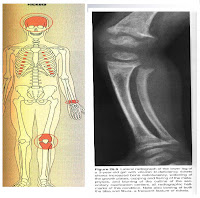

Radyoloji:

Osteopeni

Subperiostalrezorbsiyon

(elde en sık orta falankslarda, klavikuladistaluçlarında, simfizpubisve iskionkollarında)

Kafa kemiklerinde güve yeniği şeklinde lezyonlar, browntümörler

Balık vertebragörünümü

Osteitisfibrozasistikajeneralizata